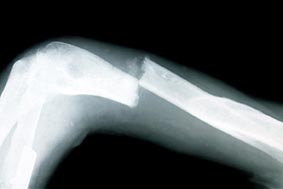

Loại nhựa mới giúp chữa lành xương gãy